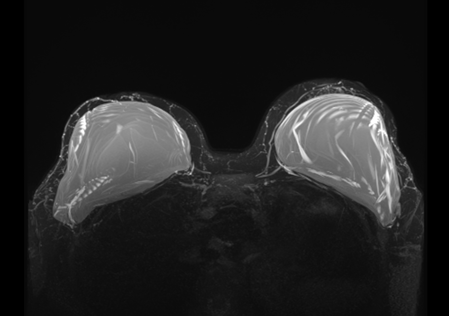

Показаниями для МРТ молочных желез являются высокая маммографическая плотность, наличие имплантов. Также это метод выбора у женщин с выявленной мутацией генов BRCA1 и BRCA2.

Рис.14 МР-томограмма имплантов молочной железы